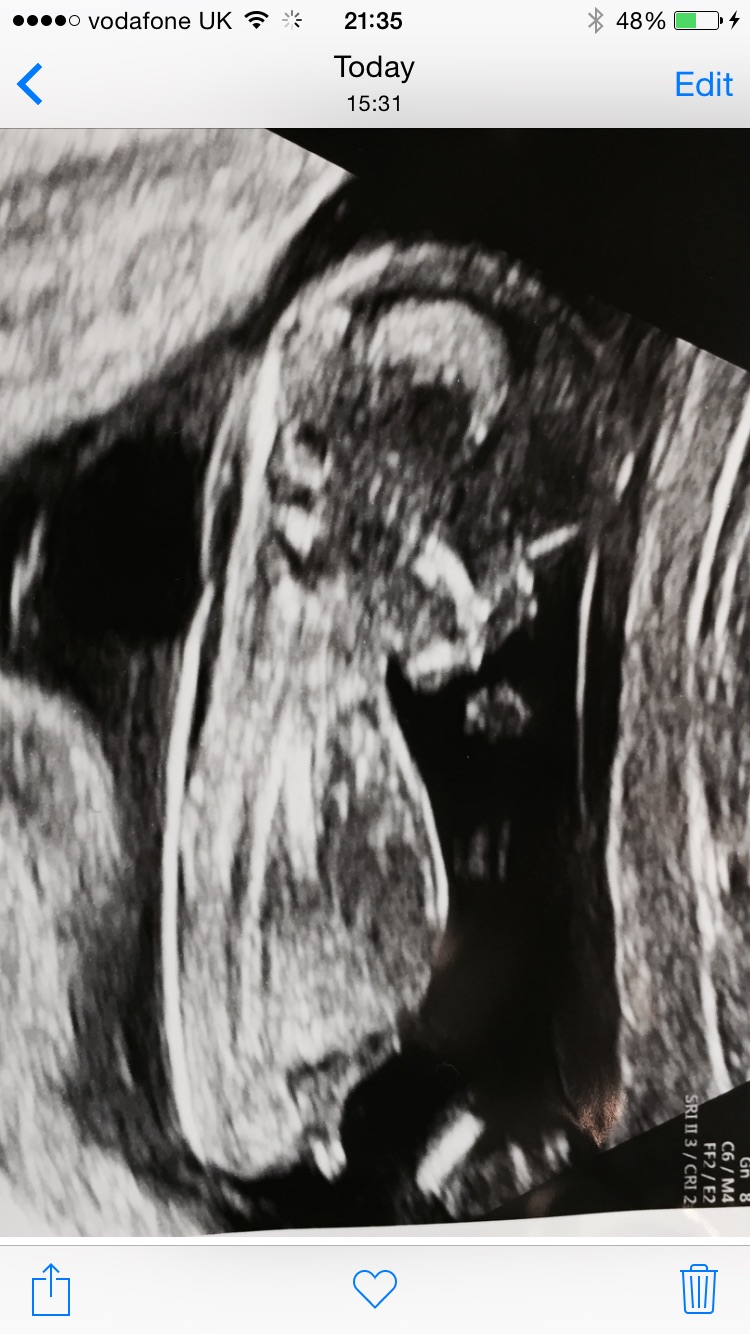

Exactly why I am torn! Can anyone use the skull theory? I don't really understand it.